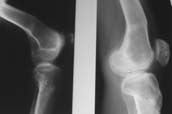

Пациент В. 53 лет, травма в феврале 2009. ДЗ. Открытый оскольчатый перелом нижней трети голени. При боли поступлении выполено ПХО, аппарат Илизарова. В последующем проводили ВХО, резекция костных отломков, укорочение 6 см, рана зажила. Была выполнена остеотомия большеберцовой кости в проксимальном отделе, резекция. Производилось тракция. На последних рентгенограммах выявлено, что одновременно с "выращиванием" регенерата произошло низведение надколенника на длину выращенного регенерата. Клинически: активное разгибание сохранено, объем движений в колене 180-110 градусов. Черными стрелками обозначен верхний край надколенника с одной и с другой стороны. Красная стрелка обозначает пальпируемую связку надколенника. Причина - остеотомия выше места прикрепления связки надколенника. Вопрос: была ли у кого подобная ситуация? Что делать? При первом обдумывании приходит решение: отсечение места прикрепления связки надколенника с костным блоком, перемещение на "правильное" место, укорочение сухожилия четырехглавой мышцы.

По снимкам - плотность регенерата хорошая, сложностей с фиксацией в него костного "основания" быть не должно.